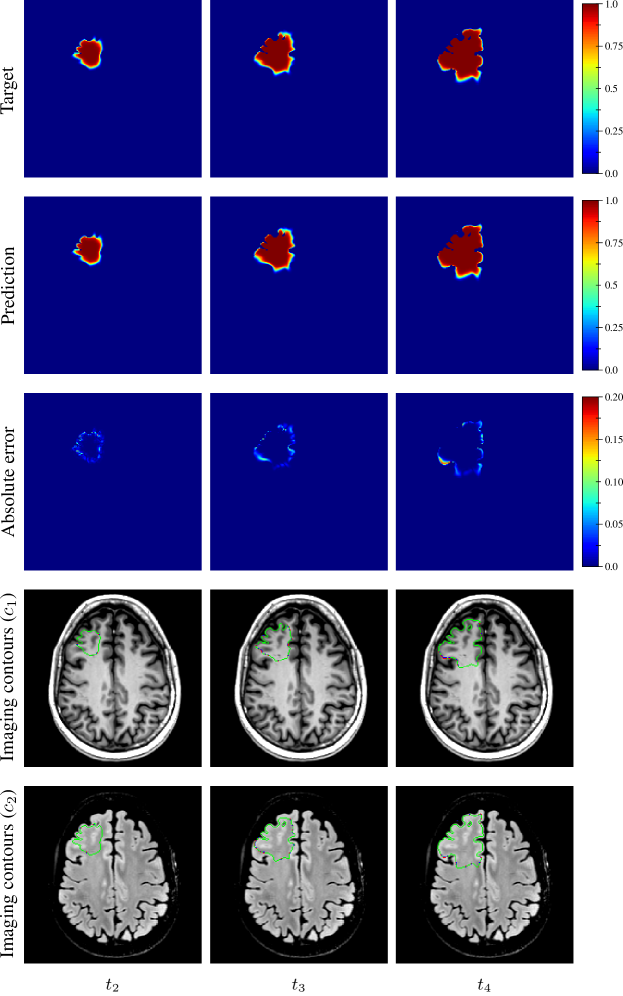

The distribution of the mean absolute error computed over the test set between the true and estimated tumour cell distributions at time t2subscript𝑡2t_{2} within the c>0.01𝑐0.01c>0.01 contour is summarised by a boxplot in Figure 7 (1st plot). The corresponding median value was 9.58×1039.58E-39.58\text{\times}{10}^{-3}. Boxplots of the Hausdorff distance and ASSD distributions computed over the test set between the true and estimated imaging contours at time t2subscript𝑡2t_{2} for threshold values c1=0.80subscript𝑐10.80c_{1}=0.80 and c2=0.16subscript𝑐20.16c_{2}=0.16 are provided in Figure 8 (1st plots). An example of true and estimated tumour cell density distributions at time t2subscript𝑡2t_{2} from the test set is depicted in Figure 9 (1st column), along with the corresponding absolute error map as well as the true and estimated imaging contours for threshold values c1=0.80subscript𝑐10.80c_{1}=0.80 and c2=0.16subscript𝑐20.16c_{2}=0.16. Additional examples are provided in Appendix C. All predicted tumour cell distributions at time t2subscript𝑡2t_{2} used in Figures 9, 7 and 8 were provided by the first network (Figure 5).

As for imaging time t2subscript𝑡2t_{2}, the distributions of the mean absolute error computed over the test set between the true and estimated tumour cell distributions at times t3subscript𝑡3t_{3} and t4subscript𝑡4t_{4} within the c>0.01𝑐0.01c>0.01 contour are summarised by boxplots in Figure 7 (2nd and 3rd plot, respectively). The corresponding median values were 1.38×1021.38E-21.38\text{\times}{10}^{-2} and 2.20×1022.20E-22.20\text{\times}{10}^{-2} for t3subscript𝑡3t_{3} and t4subscript𝑡4t_{4}, respectively. Boxplots of the Hausdorff distance and ASSD distributions computed over the test set between the true and estimated imaging contours at times t3subscript𝑡3t_{3} and t4subscript𝑡4t_{4} for threshold values c1=0.80subscript𝑐10.80c_{1}=0.80 and c2=0.16subscript𝑐20.16c_{2}=0.16 are also provided in Figure 8 (2nd and 3rd plots). The true and estimated tumour cell density distributions at times t3subscript𝑡3t_{3} and t4subscript𝑡4t_{4} are depicted in Figure 9 (2nd and 3rd column, respectively) for the same test case as for time t2subscript𝑡2t_{2}, along with the corresponding absolute error maps as well as the true and estimated imaging contours for threshold values c1=0.80subscript𝑐10.80c_{1}=0.80 and c2=0.16subscript𝑐20.16c_{2}=0.16. Additional examples are provided in Appendix C. A loss of accuracy in the estimated tumour cell density distributions over simulated time is observed in Figures 7, 8 and 9. The estimated tumour cell density distributions at times t3subscript𝑡3t_{3} and t4subscript𝑡4t_{4} used in Figures 9, 7 and 8 were computed using the reaction-diffusion model as described in Section 2.6 from (i) the cell density distribution predicted at time t2subscript𝑡2t_{2} provided the first network (Figure 5) and (ii) the predicted model parameters values provided by the second network (Figure 6).

Figure 9: Example of true (1st row) and estimated (2nd row) tumour cell density distributions at times t24subscript𝑡24t_{2-4} (1st to 3rd column, axial slices) along with the corresponding absolute error maps (3rd row) for a test tumour (d=43.47 mm2 yr1𝑑times43.47timesmillimeter2year1d=$43.47\text{\,}{\mathrm{mm}}^{2}\text{\,}{\mathrm{yr}}^{-1}$, ρ=11.22 yr1𝜌times11.22year1\rho=$11.22\text{\,}{\mathrm{yr}}^{-1}$, t1=94 dsubscript𝑡1times94dayt_{1}=$94\text{\,}\mathrm{d}$, t2=264 dsubscript𝑡2times264dayt_{2}=$264\text{\,}\mathrm{d}$). The imaging contours for threshold values c1=0.80subscript𝑐10.80c_{1}=0.80 and c2=0.16subscript𝑐20.16c_{2}=0.16 superimposed to the T1 and T2 FLAIR image are depicted in the 4th and 5th rows, respectively. The blue, red, and green segments respectively correspond to the target, prediction, and overlapping contour voxels. The predicted cell distribution at time t2subscript𝑡2t_{2} was provided by the first network (Figure 5). The estimated cell distribution at times t3subscript𝑡3t_{3} and t4subscript𝑡4t_{4} were computed using the reaction-diffusion model from the cell distribution predicted at time t2subscript𝑡2t_{2} and the predicted model parameters values provided by the second network (Figure 6).